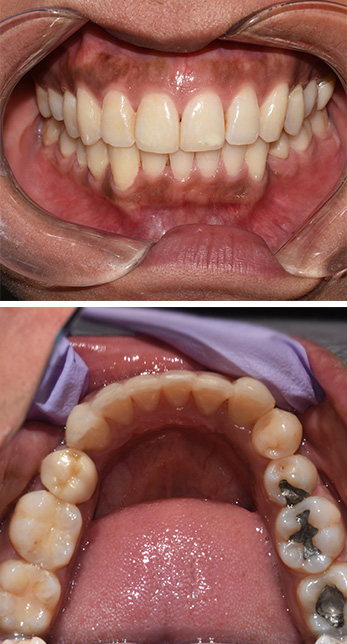

Invisalign + Ceramic Crowns

Dental Office in Amityville

Before

Cosmetic Dental Office Amityville

After